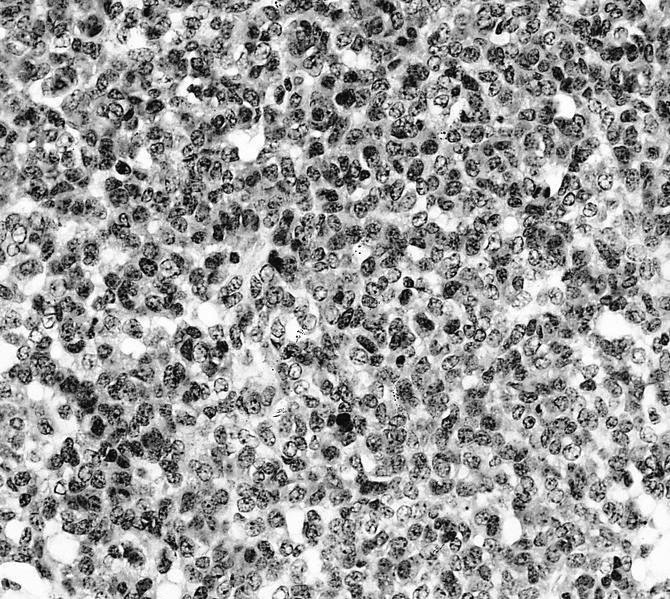

- Conventional (high grade intramedullary) osteosarcoma (Eur J Cancer 2002;38:1218, Am J Clin Pathol 2006;125:555):

- Permeative growth: intramedullary permeative growth (replacement of medullary space, surrounds and erodes native trabeculae, fills Haversian systems) and cortical destruction with soft tissue invasion

- Neoplastic cells: marked atypia (pleomorphic, hyperchromatic)

- Multiple cell morphologies often present in 1 tumor (epithelioid, plasmacytoid, spindled, small round cells, clear cells, giant tumor cells)

- Mitotic figures are easily demonstrable and atypical mitotic figures may also be identified

- Neoplastic bone (necessary for diagnosis): no minimum quantity necessary

- Most common: filigree / lace-like disorganized woven bone (intimately associated with neoplastic cells)

- Broad sheets of bone

- Normalization: decreased cytologic atypia of neoplastic cells entrapped in the bone matrix

- Scaffolding (appositional neoplastic osteoid deposition): deposition of neoplastic osteoid on native trabeculae

- Nonneoplastic giant cells: ~25% of cases

- Histologic subtypes of conventional osteosarcoma: no prognostic significance

- Osteoblastic, chondroblastic and fibroblastic are based on the prominent matrix they secrete (often admixed in 1 tumor)

- Osteoblastic osteosarcoma: the predominant matrix is neoplastic bone (as described above)

Microscopic (histologic) images

Contributed by Jesse Hart, D.O., Borislav A. Alexiev, M.D. and AFIP

A 16 year old boy had a biopsy from a 16 cm mass in the proximal humerus (see image). Which of the following is true?

Practice answer #2

C. Treatment will include neoadjuvant chemotherapy followed by resection. This is a conventional high grade osteosarcoma.